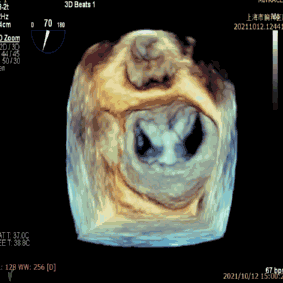

手术于全麻下进行,手术采用经典股静脉房间隔途径,房间隔穿刺后置入24F导引导管及二尖瓣夹输送系统,在TEE引导下准确植入一枚二尖瓣夹,瓣膜夹位置稳定,植入后反流基本消失(图2),二尖瓣跨瓣平均压力阶差2mmHg,双孔化形成,遂移除器械输送系统。患者术后恢复良好,瓣膜夹位置稳定,患者当晚即表现出多年久违的“安然入睡”。拟于近期出院。

图2:术后TEE提示,二尖瓣夹植入后反流基本消失,双孔化形成